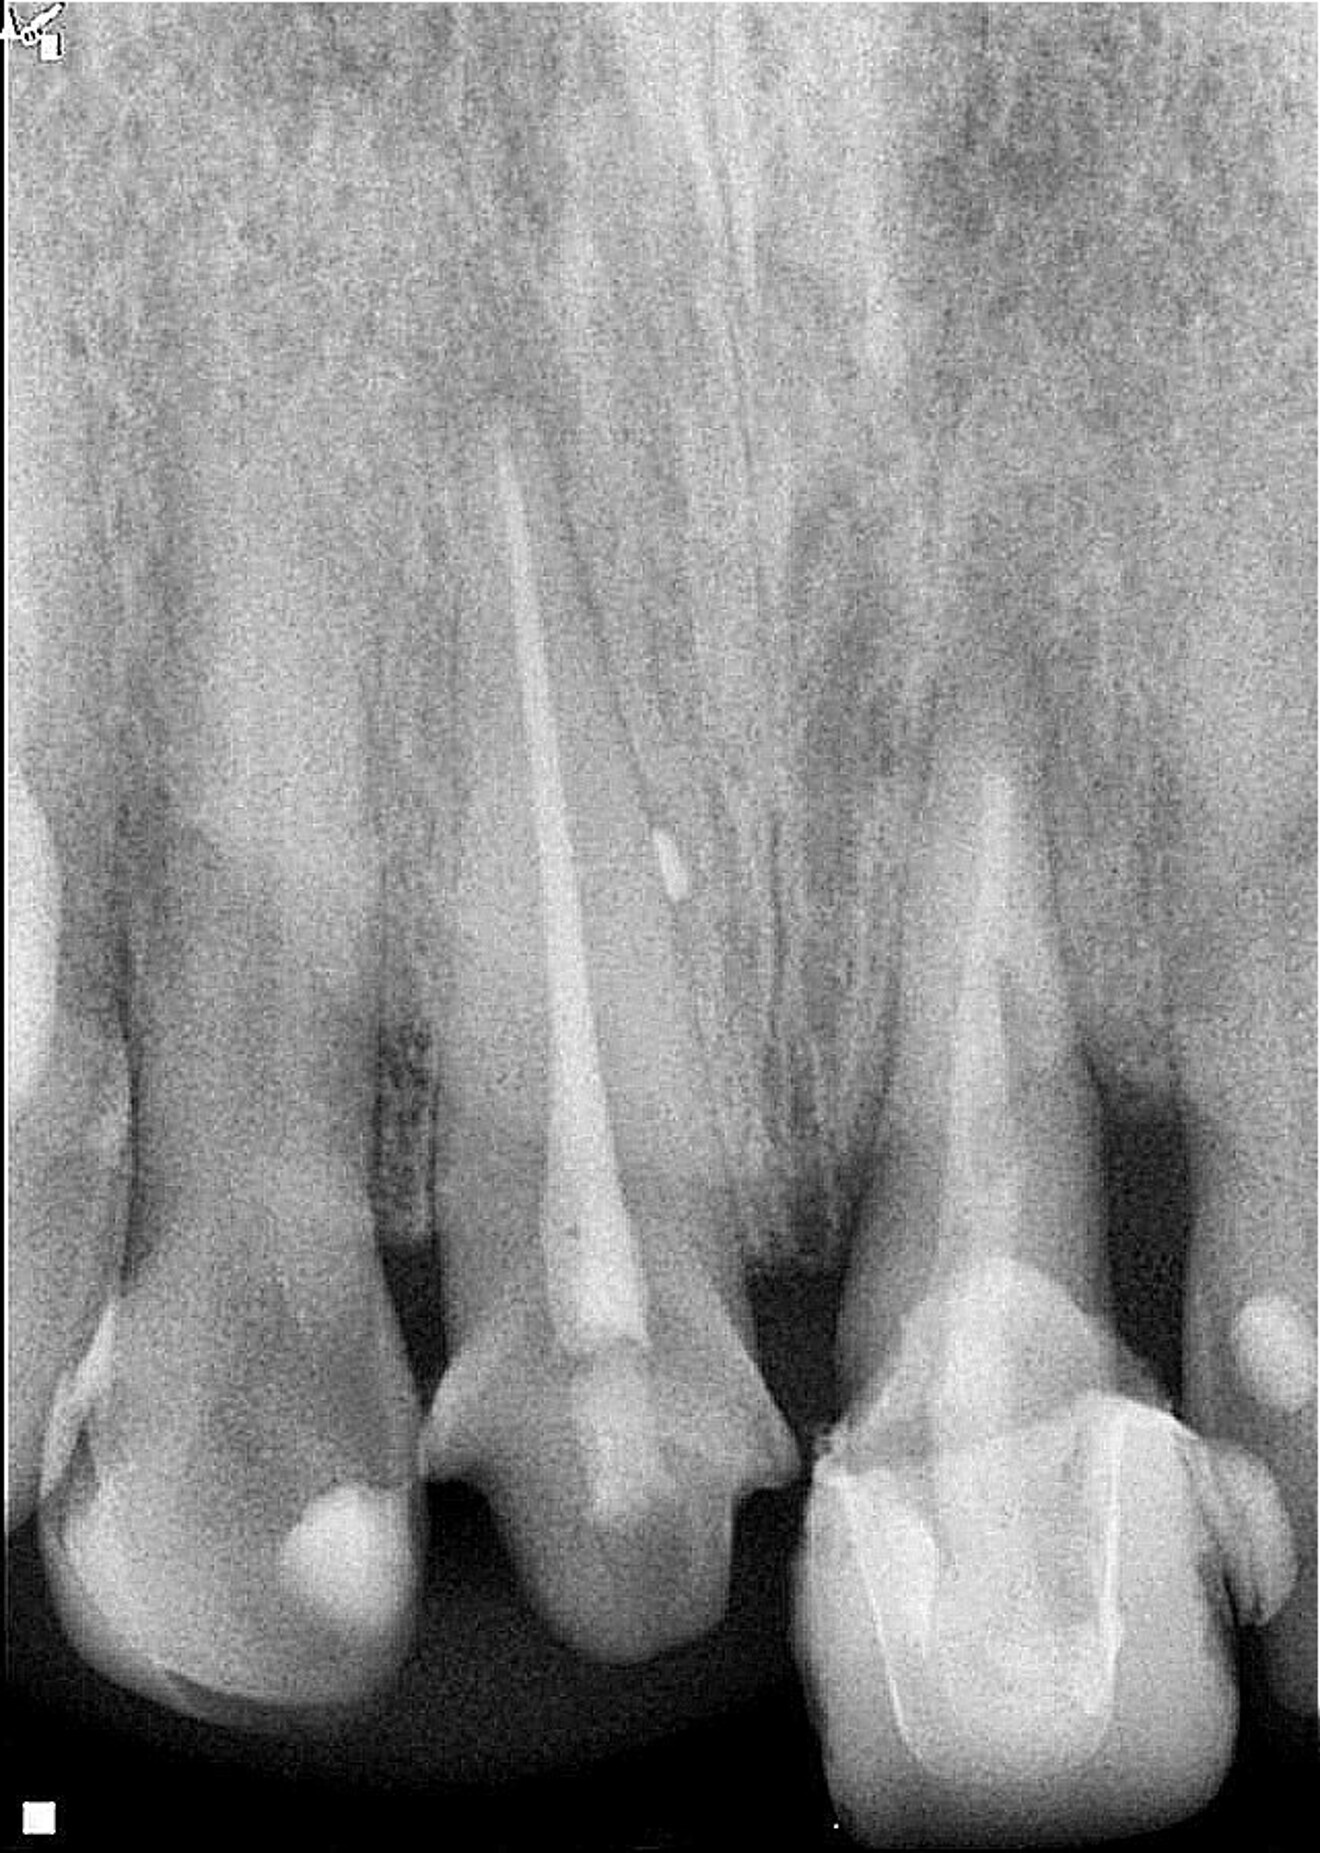

Radiographic examination conducted two years after the extrusion revealed good periapical healing and ongoing vertical bone growth at the interdental bone crest, mainly in the distal area (Fig. 5). It has been reported that a normal periodontal ligament contour may be observed three months postoperatively,6, 8, 20 and periapical repair and resolution of radiolucency are commonly seen six months later, as well as minimal marginal bone loss,6 often associated with bone damage incurred during the extrusion process. After two years of follow-up, complete repair of the periapical tissue and ongoing bone remodelling mainly in the area of the distal bone crest were observed (Fig. 6). The tooth remains asymptomatic, non-mobile, and fully functional aesthetically and biologically (Fig. 7). The radiographic situation after the four-year follow-up period showed stable results (Fig. 8).

Fig. 5: Two-year follow-up radiograph showing periapical healing and signs of bone remodelling, mainly vertical bone growth in the distal area.